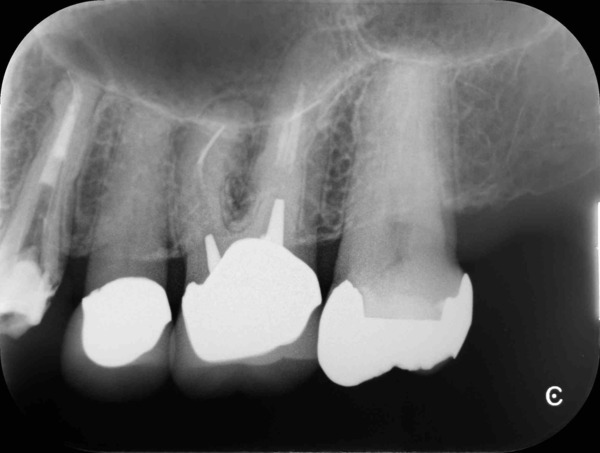

術直後のデンタルX線写真です。

ここから1ヵ月ほど経過を診させていただきました。

術後1ヵ月のデンタルX線写真です。

自覚症状はなく、レントゲン写真でも異常所見は認めません。

この歯は虫歯で削った部分が大きかった為、型どりを行い、部分的に被せる治療を行いました。